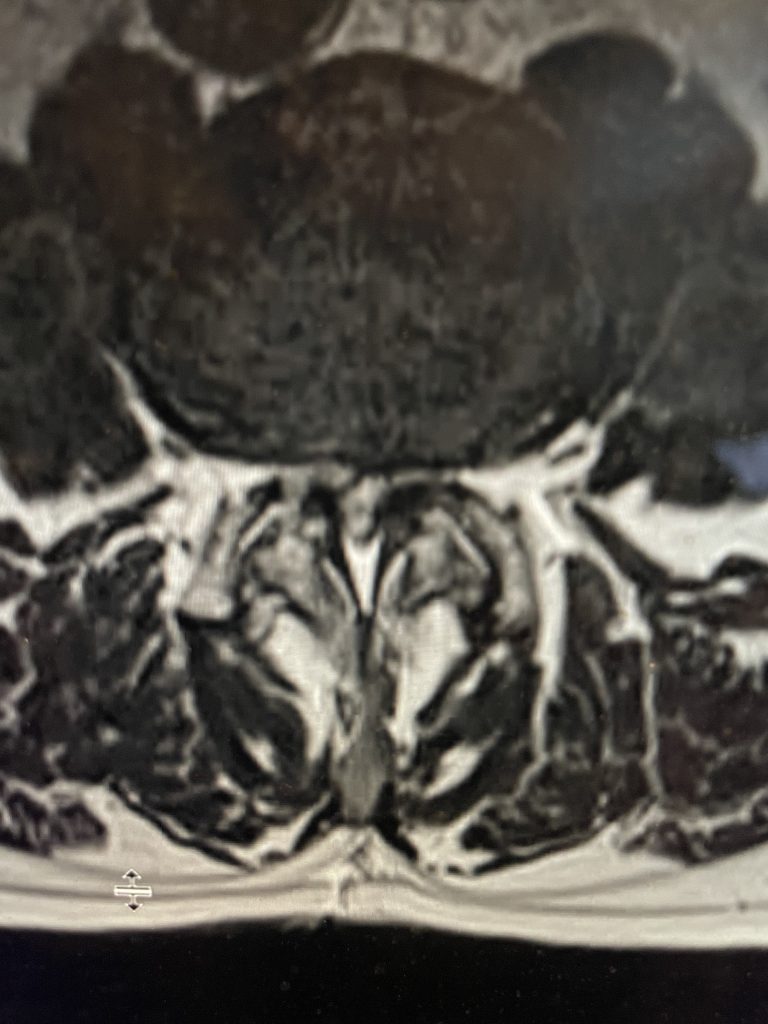

Figure 2. Axial T2-weighted MRI demonstrating severe concentric stenosis at L3-4 due to severely enlarged facet joints and ligamentous hypertrophy

MRI demonstrated severe L3-4 stenosis with a grade 1 spondylolisthesis. He also had L2-3 stenosis. (Fig 1). On axial MRI (Fig 2) he had severe concentric stenosis at L3-4, but on careful examination it appeared that the right side had particular distortion of the anterior aspect of the thecal sac, perhaps secondary to a facet cyst. It seemed more likely coming off the facet joint and not a disc herniation. Although the right side was worse, most of his symptoms were on the left. Why does that happen? I don’t have a great explanation. Clearly the left side is also compressed but sometimes the body just chooses the side to be affected symptomatically when both sides are involved. This is true for compression of the spinal cord for instance in the cervical spine. What is not right, however, is that if a patient has a lateralized disc herniation and the opposite side is symptomatic and without compression, then one should not offer surgical treatment unless that disc is causing severe compression on one side with just less compression on the ipsilateral symptomatic side. Then one can argue that the pathology is having an effect on the opposite side if there is some degree of bilateral compression even if the ipsilateral symptomatic side is less compressed.